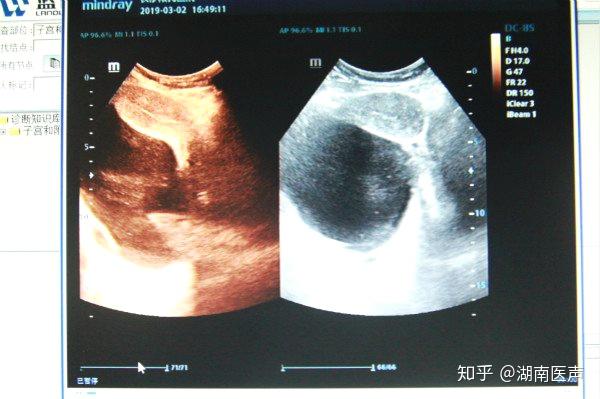

右侧盆腔内包块(残角子宫并宫腔内积血,输卵管扩张积血,盆腔内积血?).

停经,腹痛剧烈,妊娠实验阳性,b超提示附件区包块,宫外孕?